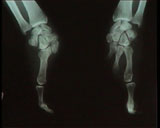

COMMENT UN HOMME ATTEINT DE MONODACTYLIE CONGENITALE SYMETRIQUE

En février 1998, un homme de 43 ans, atteint d'une monodactylie bilatérale congénitale (un seul doigt à chaque main), s'est présenté à la consultation de Médecine aéronautique du CHU d'Amiens pour demander s'il lui serait possible d'apprendre à piloter un avion. En tant que médecin agréé et instructeur-avion, et après un examen général, nous avons constaté combien cet homme était habile à conduire sa propre voiture non modifiée et lui avons donné un baptême de l'air technique. Ainsi, nous avons pu répondre positivement à la question du patient et entreprendre nous-même sa formation. L'entraînement pour le brevet de base a duré 2 ans, et a comporté plus de 30 heures de vol et 3 tests successifs avec l'Inspecteur-contrôleur de Picardie, Patrick Delfolie. Le Conseil médical de l'Aéronautique Civile (CMAC) a donné un avis favorable. Grâce à cette dérogation, l'intéressé a poursuivi avec succès sa formation et a obtenu son brevet de pilote privé avion. Il peut dès lors emmener amis et passagers de son choix en vol local ou en voyage dans le monde entier, à condition de garder l'entraînement en vol minimum règlementaire. Connaissance du handicap et mise en pratique des capacités d'adaptation du patient ont permis de mener à bien cette expérience.